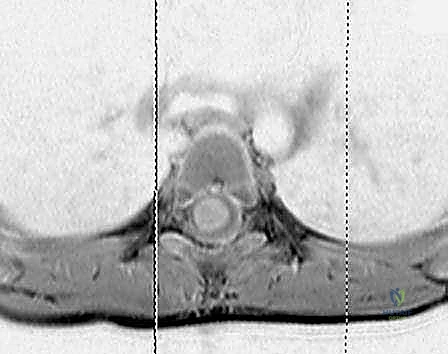

- الرنين المغناطيسي (MRI): يُستخدم في حالات محددة لتقييم الأنسجة الرخوة، الأربطة، أو لاستبعاد تشوهات الحبل الشوكي.